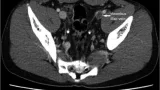

テーマは「紡錘型細胞脂肪腫」.